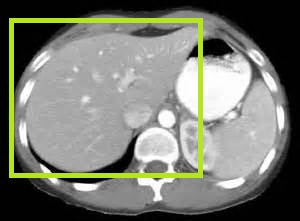

Компьютерная томография – метод, хорошо показывающий структуру твердых тканей. Для визуализации мягкотканого компонента проводится контрастирование. При планировании оперативного вмешательства требуется трехмерное моделирование (3D-реконструкция).

Контрастное усиление назначается при метастазах печени при наличии первичных опухолей разных локализаций. Мультиспиральное сканирование применяется при совместном изучении органов брюшной полости, гепатобилиарных структур.

Назначение компьютерной томографии печени и желчного пузыря распространенно в онкологии, так как метод выявляет большинство видов опухолей данных систем. С помощью компьютерной томографии осуществляется контроль введения иглы при взятии биопсийного материала.

Компьютерная томография печени позволяет диагностировать причину болей, возникших в ней. Во время ее проведения рентгеновские лучи воздействуют на органы брюшной полости, в которой разные ткани поглощают лучи в разной степени.

Компьютерная томография предоставляет врачу снимки тонких срезов органов брюшной полости. На них видно трехмерное изображение:

- опухоли, кровеносных сосудов, желчевыводящих путей;

- органов, которые окружают печень (почки, селезенка, поджелудочная железа, забрюшинные лимфатические узлы.